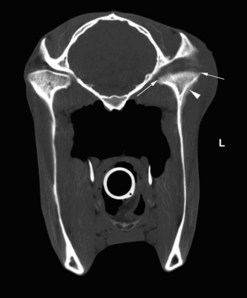

Dorsoventral projection (Figs 13.1213.13)

This view is quite easy to obtain in the sedated horse and is particularly useful for visualizing the ventral conchal sinus, nasal cavities, and nasal septum. Additionally, it can be used for evaluating maxillary/mandibular fractures; bony distortion of the maxilla associated with periapical infection of the rostral cheek teeth or intra-sinus masses. Laterally or medially displaced teeth and fractured maxillary teeth (particularly sagittal fractures) can also be visualized with this view; however, these abnormalities should be apparent during a thorough oral examination. The extremely dense bone of the hemimandibles makes it almost impossible to evaluate normally positioned mandibular cheek teeth using this projection.

An increased exposure is required for this projection compared to those used for lateral or lateral-oblique views of the skull. The X-ray beam is directed perpendicular to the dorsal plane of the head (which runs parallel to the hard palate) with the cassette held parallel with the ventral mandible and positioned as caudally as possible (Fig. 13.12). Because the mandibular cheek teeth rows are so close together (anisognathia), even a small degree of obliquity obscures one nasal cavity, ventral conchal sinus, and maxillary cheek teeth row and prevents accurate comparison of left and right maxillary sinus opacity; therefore, great care must be taken to ensure that the head is absolutely straight and the beam perpendicular to the dorsal plane. The centering point is in the midline of the dorsal aspect of the head at the level of the rostral aspect of the facial crests. Collimation of the primary beam should include the left and right lateral extents of the skull, the caudal aspects of the bony orbits and the diastemata, rostrally (Fig. 13.13).